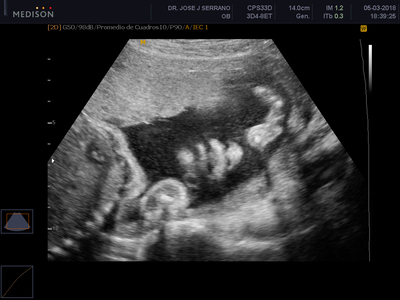

La ecografía anatómica o morfológica es una ecografía que se realiza entre la semana 18 y 24 de la gestación. En la mayoría de casos se la hace por vía abdominal y no es una prueba invasiva. Esta evaluación es imprescindible puesto que es en este momento en que el feto ya ha crecido lo suficiente como para poder hacer un diagnóstico o descarte de anomalías y malformaciones fetales.

La ecografía morfológica debe hacerse en estas semanas porque es el momento ideal para hacer un estudio minucioso del feto, en la medida en que las condiciones físicas son perfectas para permitir un estudio a través de esta herramienta. En esta etapa, el feto mide entre 14 y 16 centímetros, y pesa más o menos 250 gramos. Es lo suficientemente grande para distinguir sus estructuras correctamente, pero es lo suficientemente pequeño para moverse libremente en el útero.

Esta ecografía busca detectar anomalías fetales explorando detalladamente cabeza, cara, tórax, abdomen, genitales y extremidades, así como todos los órganos del bebe (cerebro, corazón, pulmones, riñones, etc). También se tomarán las medidas fetales para compararlas con el tiempo de embarazo y descartar problemas de desarrollo y crecimiento. Además, se evaluarán los movimientos del feto, su patrón de respiración, tono fetal, flujo sanguíneo, entre otros.